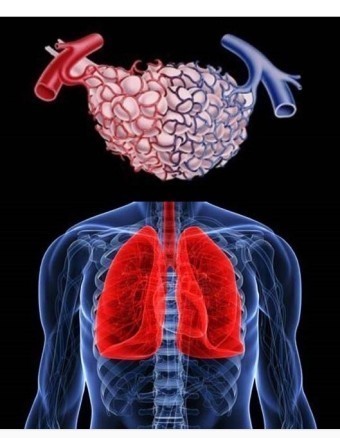

기흉은 폐의 표면과 흉벽 사이에 공기가 축적되는 상태를 말합니다. 이로 인해 폐가 충분히 팽창하지 못해 호흡 곤란과 통증을 유발합니다. 기흉은 자발적으로 발생할 수 있으며, 외상에 의해서도 발생할 수 있습니다.

기흉의 증상 기흉 증상은 흉통과 호흡곤란이 대표적입니다.

흉통은 대체로 갑자기 시작되며 24시간 정도가 지나면 사라집니다. 사람마다 흉통을 다르게 느낄 수 있는데, 등 쪽에서 담이 결린다고 하거나 숨쉴 때 가슴 통증이 느껴진다고 합니다.

호흡곤란은 환자의 상태에 따라 다르게 나타나며, 기존에 폐질환이 없는 사람의 경우 대체로 호흡곤란이 심하지는 않습니다. 하지만 기흉 증상이 심한 환자는 호흡이 불편할 정도의 호흡곤란을 느끼며 청색증이 동반될 수 있습니다.